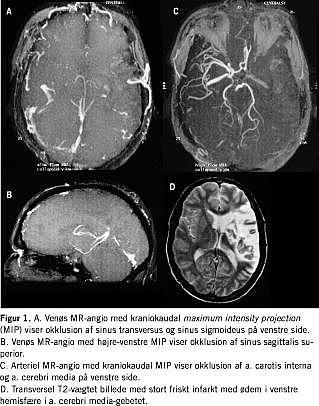

Fire år senere blev han genindlagt med afasi og højresidig hemiparese. En MR-skanning af cerebrum viste total venstresidig mediainfarkt på basis af en høj carotis interna okklusion påvist ved MR-angiografi (Figur 1 ).

Kort tid efter forværredes tilstanden, og ny MR-skanning af cerebrum viste total sinus sagitalis superior-trombose, trombose af sinus transversus og sinus sigmoideus på venstre side (Figur 1). Trods antikoagulansbehandling blev patienten tiltagende bevidsthedssvækket, og mors indtrådte få dage senere.